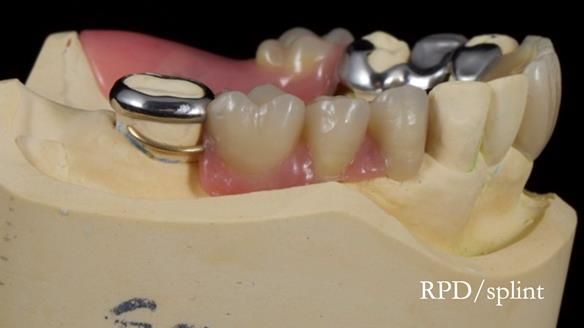

This edition features the case of Edgar, who sought help for a poorly fitting, acrylic-based partial denture that rocked, affected his speech, and caused discomfort. After considering various treatment options, including dental implants, Edgar opted for a metal-based removable partial denture, designed by myself with input from my technician, Rowan Garstang.

Despite significant improvements in comfort and aesthetics, Edgar expressed dissatisfaction with the denture's slight movement during certain jaw movements. This case underscores the importance of setting clear expectations, communicating limitations early, and ensuring both the patient and I are aligned on what can realistically be achieved. I must also be careful not to exaggerate the benefits of the treatment, to avoid creating false expectations.

Treatment Process: I provided the clinical work while Rowan Garstang delivered the technical aspects. The treatment required fifteen visits to fit and review Edgar.